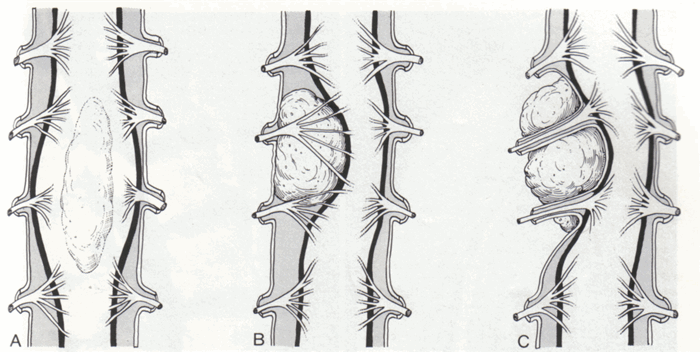

Опухоли спинного мозга подразделяются на интрамедуллярные (в паренхиме спинного мозга) и экстрамедуллярные (вне паренхимы).

В группу первичных опухолей включают новообразования исходящие из мозгового вещества (интрамедуллярные опухоли) и развивающиеся из оболочек мозга, корешков, сосудов (экстрамедуллярные опухоли). Экстрамедуллярные опухоли встречаются значительно чаще, чем интрамедуллярные.

Новообразования резко нарушают функционирование спинного мозга, сдавливая (менингиома, невринома), разрушая (метастаз рака) или прорастая (глиома) его вещество. Любые опухоли уменьшают пространство в позвоночном канале, нарушая крово- и ликворообращение.

Синдром частичного, а затем полного поперечного поражения спинного мозга при экстрамедуллярных опухолях является следствием его сдавления, возникновения функционально-динамических нарушений, затем необратимых дегенеративных изменений, сначала в проводящих путях, а по мере увеличения опухоли – и в сером веществе. При интрамедуллярных опухолях этот синдром обусловлен разрушением или сдавлением серого вещества в соответствующем сегменте и нарастающим сдавлением изнутри белого вещества спинного мозга. Развитие синдрома поперечного поражения спинного мозга до параплегии может продолжаться от нескольких месяцев (при злокачественных опухолях) до 1,5-3 лет (при доброкачественных).